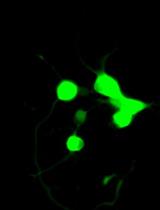

Dynamic light scattering analysis showed that the average sizes for blank nLNPs (Figure 3) and IL-22/nLNPs (Figure 5) are 189.9 ± 69.3 and 184.2 ± 84.96 nm, respectively, based on triplicate measurement.

Figure 3. Measurement of size in blank nLNPs. Particle size was determined to be 189.9 ± 69.3 nm in diameter.

Figure 5. Measurement of size in IL-22/nLNPs. Particle size of IL-22/nLNPs was 184.2 ± 84.96 nm in diameter.